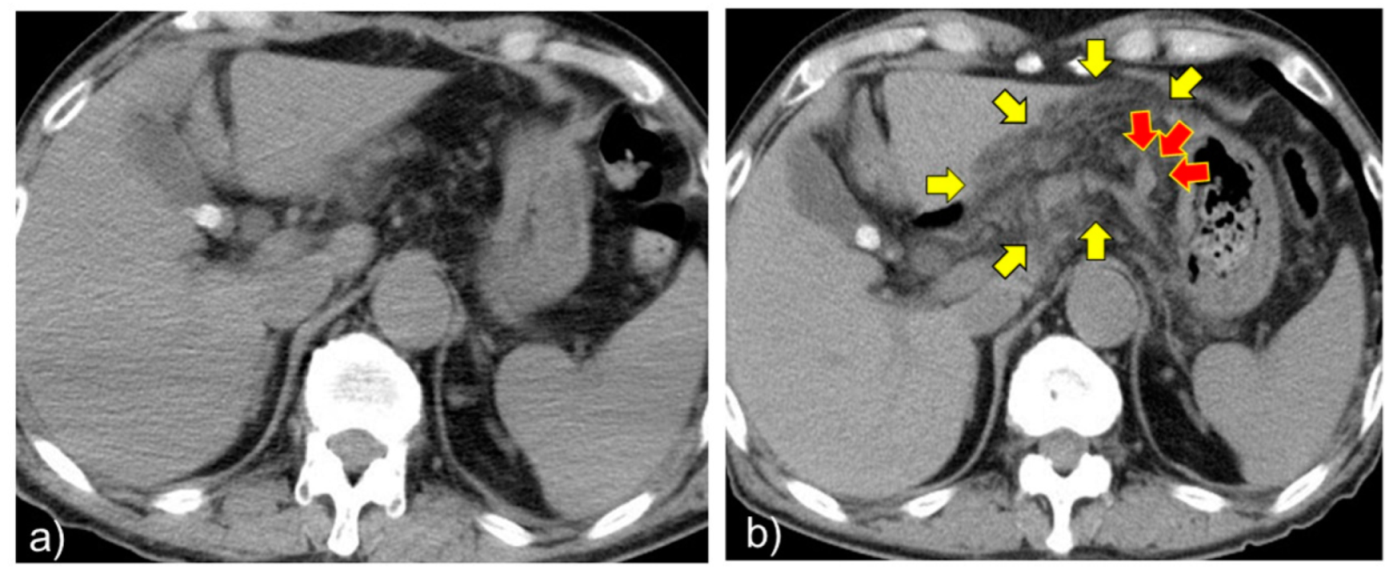

2. Case Presentation